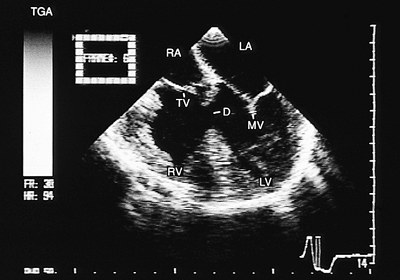

Discordant Ventriculoarterial Connection

V–A discordance, or complete transposition of great vessels, is the condition in which the aorta is connected to the right ventricle and the pulmonary artery to the left ventricle, although the A–V connection is concordant. In this anomaly the aorta is located in front and to the right of the main pulmonary artery. However, this abnormal spatial relationship of the semilunar vessels is not constant; in approximately 20% of cases the aorta is found in different positions depending on the orientation of the infundibular septum.

The echocardiographic diagnosis of this malformation should include both morphologic and functional aspects. Following segmental sequence, situs and the type of A–V connection should be clarified. V–A discordance should be established, with conventional transthoracic recordings and transesophageal exploration used to aid in clarifying some specific alterations. Conditions discussed in the following paragraphs can be detected with this technique.

In images in the transverse plane at the level of the great arteries, the vessel that is anterior and to the right can be seen to correspond to the aorta and the posterior left vessel to the main pulmonary artery (Fig. 8.2.42). In these images, confirmation that the aorta is connected to the ventricle that receives systemic venous return is obtained by demonstrating that the anterior vessel opacifies when saline solution is injected into a peripheral vein. In progressively superior sections, the posterior vessel can be recognized as corresponding to the pulmonary artery because it bifurcates early. It is easy to demonstrate valvular or subvalvular pulmonary stenosis, or both, using color Doppler (Figs. 8.2.43 and 8.2.44).

FIGURE 8.2.42. Discordant ventriculoarterial connection. In the presence of transposition of the great arteries (TGA), transverse plane imaging makes it possible to recognize the connection of the right ventricle (RV) with the aorta (AO) and the left ventricle (LV) with the pulmonary artery (PA). An anomalous insertion of the mitral valve (MV) produces subvalvular pulmonary obstruction. The pulmonary valve opening is also restricted. LA, left atrium; RA, right atrium; VS, ventricular septum.